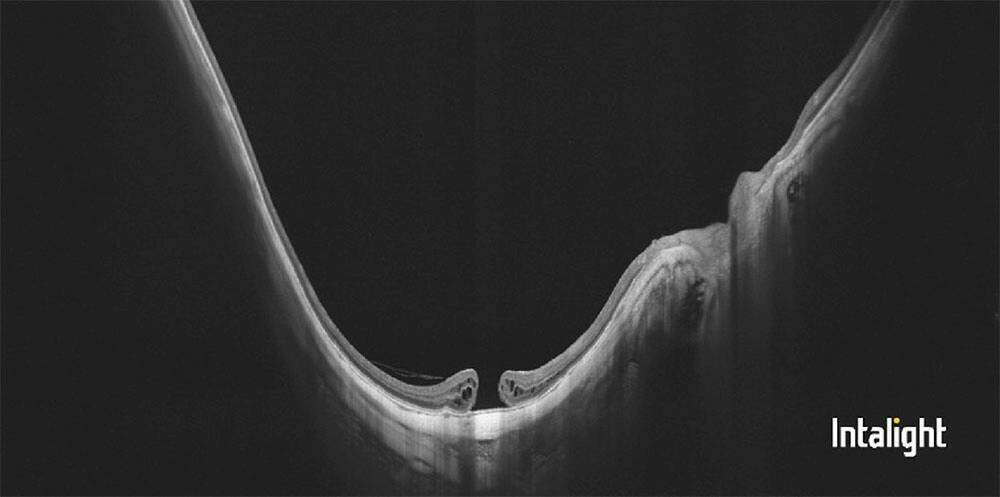

Figure 2. Le trabéculum juxtacanaliculaire dans la pince lors d’une sclérectomie profonde. C’est ce trabéculum qui offre 80 % de la résistance à l’écoulement de l’humeur aqueuse par la voie trabéculaire.